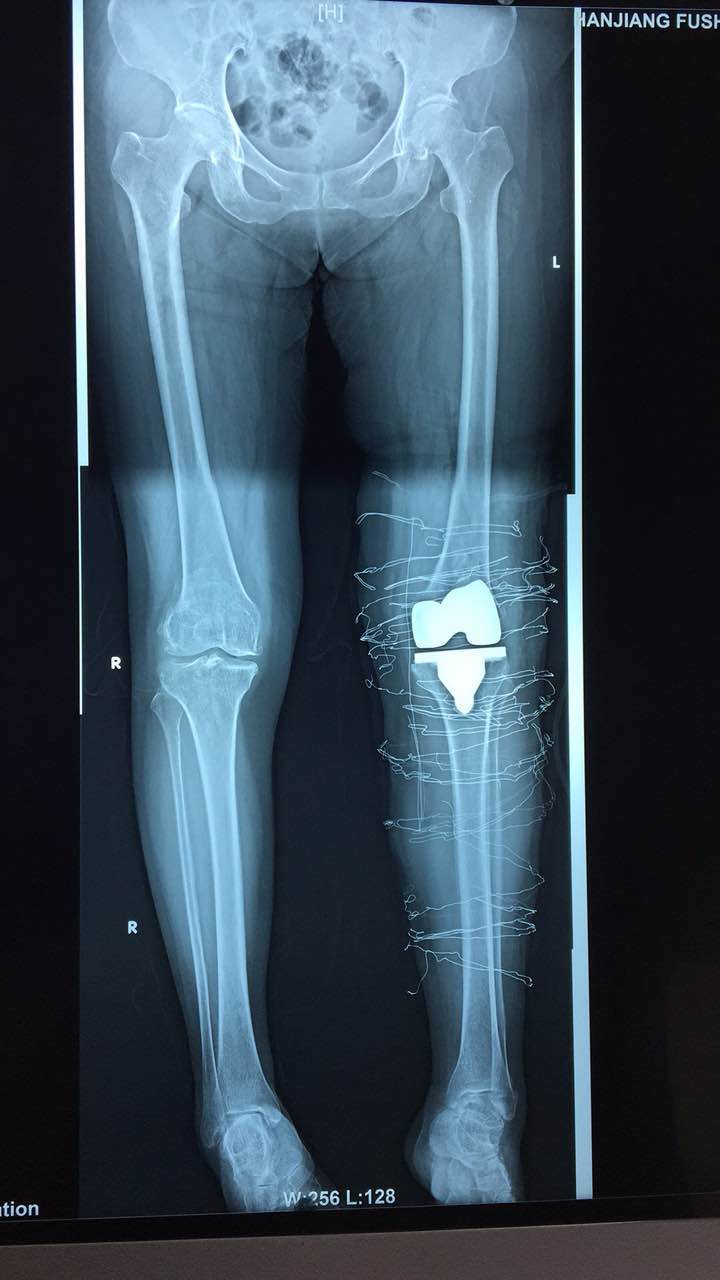

患者术后影像资料